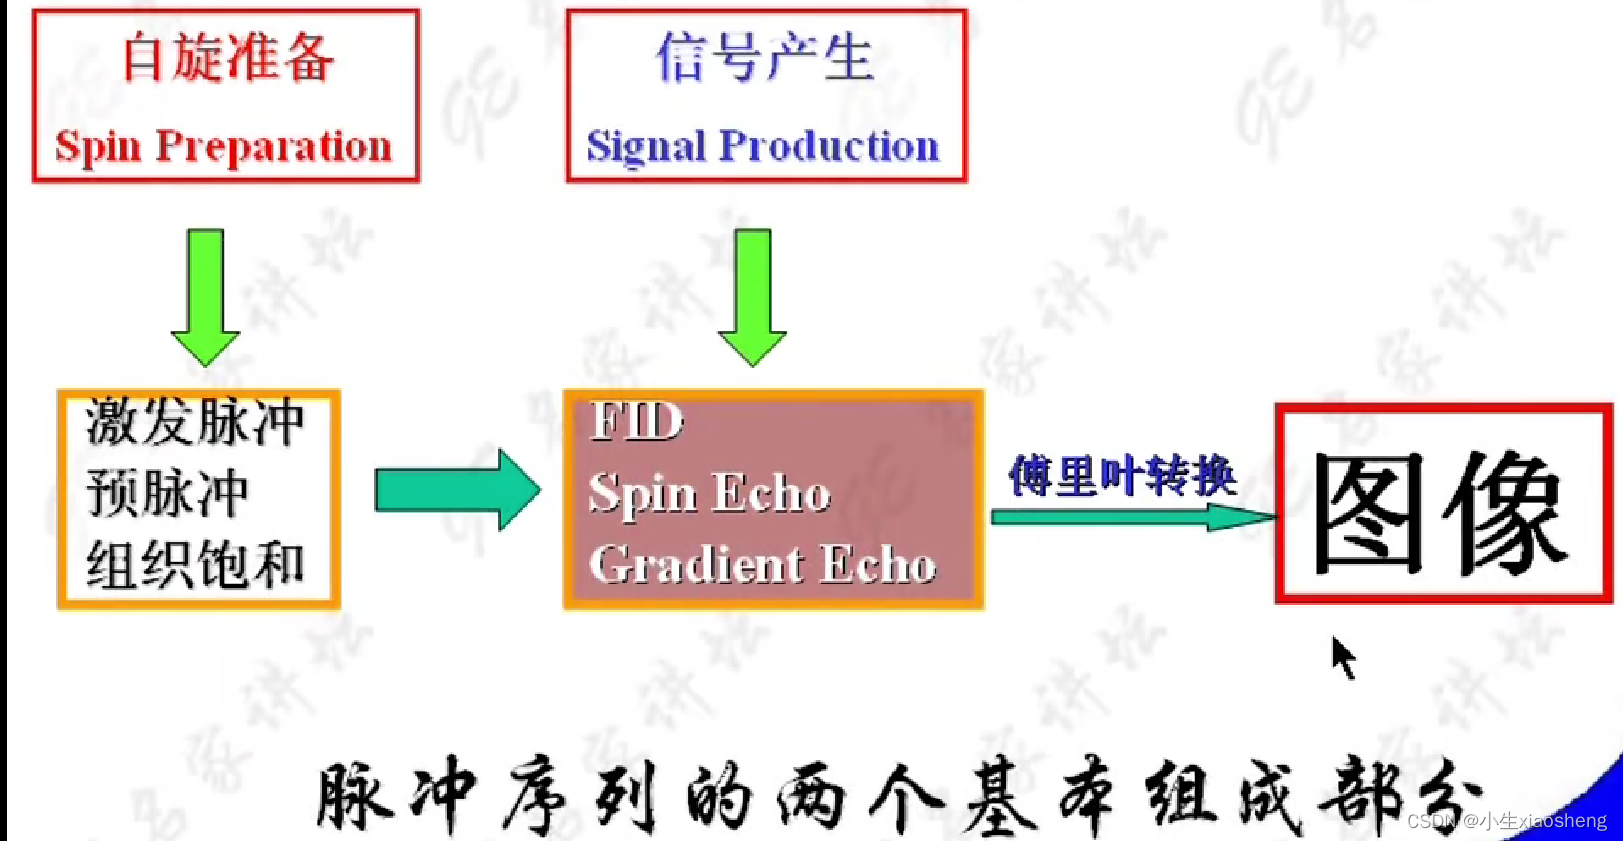

自旋回波--90度和180度填充K空间;反转恢复--在自旋的基础上两边加180度;梯度回波--消除每次脉冲留下的影响,以及波的次数;propeller==》K空间填充技术和FSE或FIR结合用于减少运行伪影;EPI==》采集方式,一次激发采集多个回波的形式但与单次不一样;PRESTO和GRASE==》前面几种的一种结合形成新的。